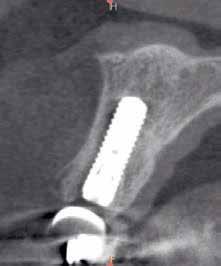

Egy fiatal páciens jelentkezett nálunk, akinek eltörött a szabad véggel rendelkező hídja (1. ábra). A hiányzó, első premoláris fog esetén implantációs pótlást javasoltunk. A csontállomány értékeléséhez CBCT-vizsgálatot végeztünk, és az elemzéséhez NNT Viewert (NewTom) használtunk, és copaSKY 4×10 mm-es (bredent medical) implantátumot választottuk a fog pótlásához

1. ábra: Műtét előtti fogászati panorámafelvétel, amelyen a hiányzó felső állcsont jobb első premolárisát és a szabad véggel rendelkező hidat láthatjuk. — 2. ábra: Az implantátum méreteinek megtervezése CBCT-vel. 3. ábra: Bukkális lágyrészdefektus. — 4. ábra: A biológiai szélesség értékelése a vertikális lágyszövetvastagság alapján. 5. ábra: Palatinális „tekercslebeny” – Palatal roll flap. — 6. ábra: Bredent medical copaSKY 4x10 implantátumbeültetés. 7. ábra: Szubkresztális implantátumbeültetés a várható biológiai szélességnek megfelelően.

(2. ábra). A lágyszövetek értékelése Seibert szerinti I. osztályú csontdefektust állapított meg (3. ábra), ezért a beavatkozáskor palatinális „tekercslebenyt” preparáltunk (palatal roll flap), és implantációt végeztünk, hogy kompenzálni tudjuk a bukkális lágyszövet-behúzódást. Megmértük a vertikális lágyszövetvastagságot, és úgy terveztük, hogy a szubkresztális implantátum beültetése összhangban legyen a biológiai szélesség kialakulásával a transzgingivális gyógyulási periódus alatt (4. ábra)